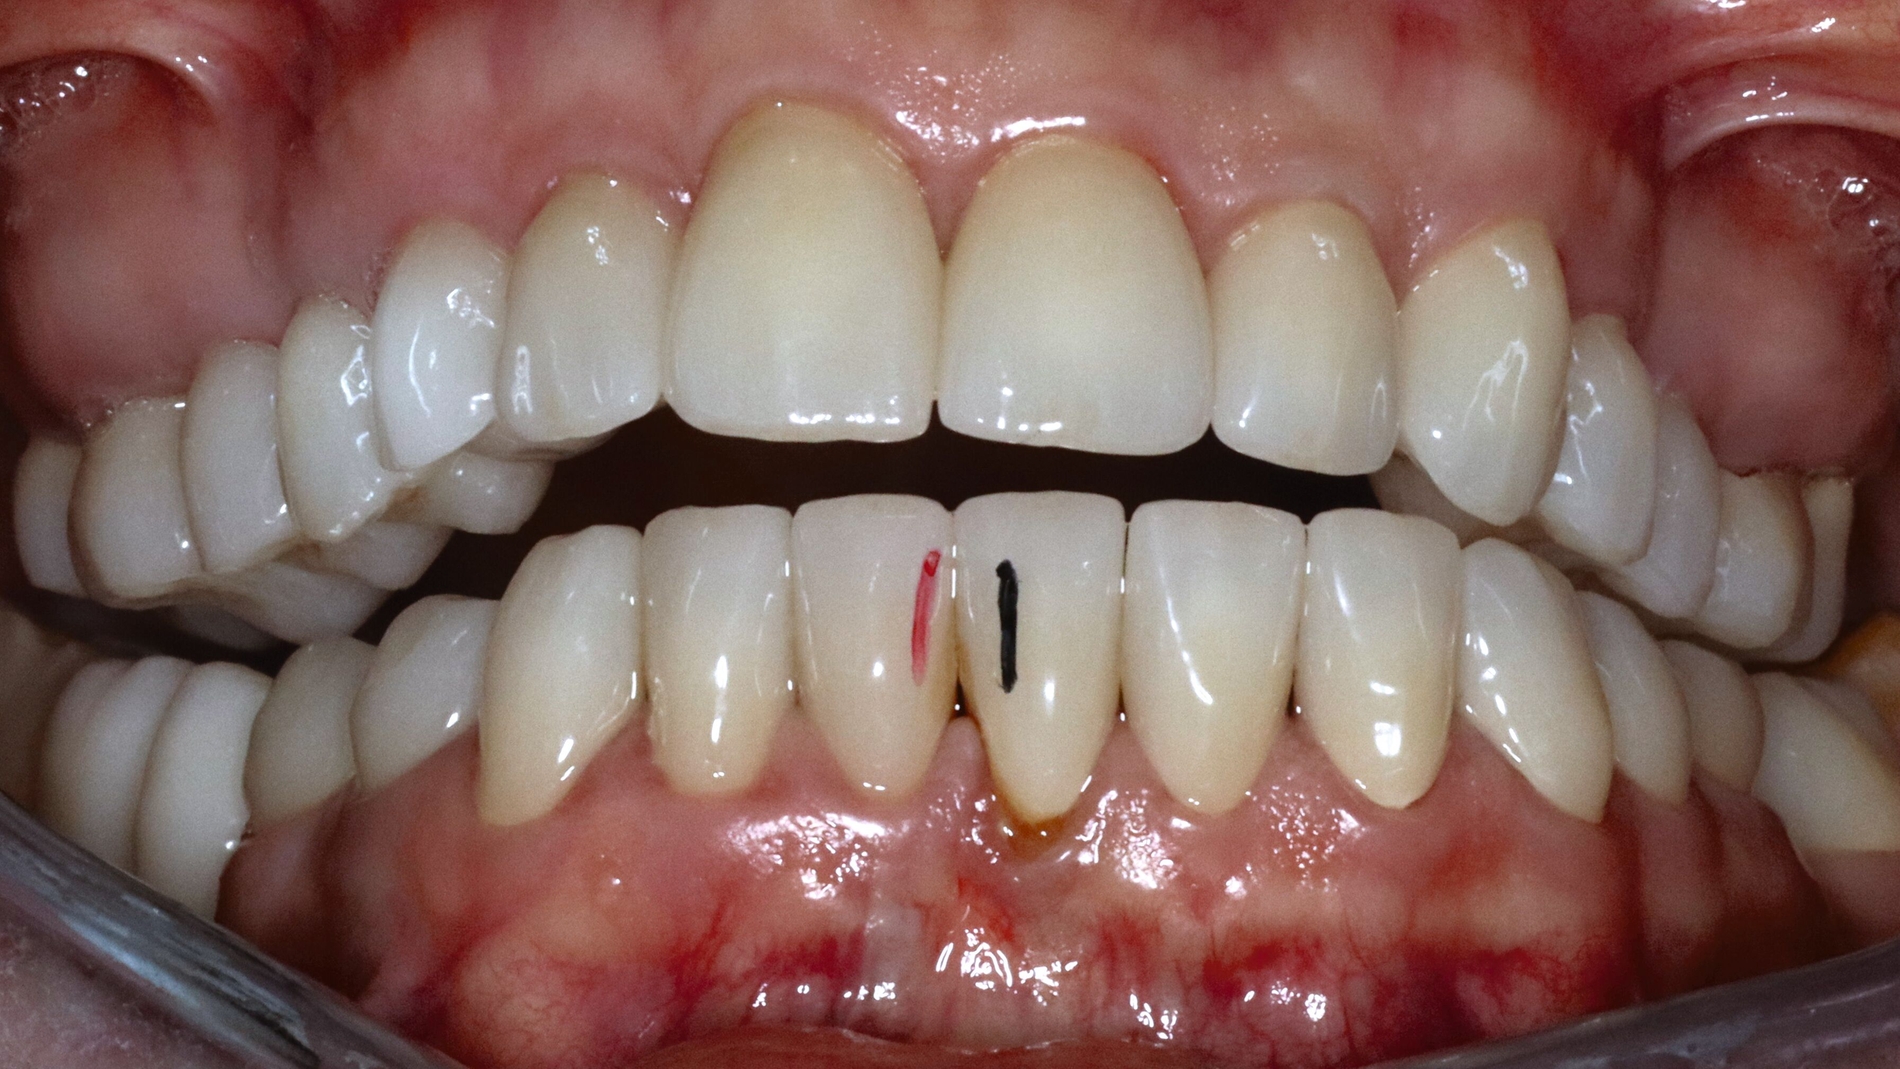

Die Patientin schilderte eine deutliche Instabilität des Zusammenbisses mit punktuellem Kontakt auf der linken und fehlenden Zahnkontakten auf der rechten Seite seit dem Tag der Insertion des Zahnersatzes. Ein annähernd stabiler Zahnkontakt sei nur durch aktiven Verschub des Unterkiefers nach rechts im Sinne eines Eingleitens in die Interkuspidation des Zahnersatzes erreichbar. Bei Provokation dieser „schiefen“ Unterkieferposition komme es jedoch aufgrund der muskulären Anstrengung nach kurzer Zeit zu Beschwerden. Die Patientin gab in diesem Zusammenhang Schmerzen und eine Grundanspannung der Kau-/Nackenmuskulatur und Kopfschmerzen an, jeweils links > rechts (Abbildung 4).

Die Sprechfunktion und die Funktion der mimischen Muskulatur (zum Beispiel Küssen) beschrieb sie als anstrengend und ermüdend. Die Kieferöffnung verlaufe schräg nach links und sei schmerzhaft eingeschränkt. Aufgrund der instabilen Zahnkontakte sei die Kaufunktion deutlich limitiert und beschwerlich. Im Bereich der linken Vorkontakte komme es wiederholt zu Einbissverletzungen und mechanischen Irritationen der Wangeninnenseite. Ebenso wurden Schmerzen im Zungenbereich links und zeitweise Empfindungen von Taubheitsgefühl beschrieben. Als ein weiteres Problem nannte die Patientin, dass der linksseitige Vorkontakt der Kronen dauerhaft bestehe und ein Nichtkontakt im Sinne einer Ruhelage nur durch kontinuierliche aktive Kieferöffnung möglich sei.

In der Funktionsanalyse wurden die folgenden Befunde erhoben:

Palpation der Kiefer- und Nackenmuskulatur links > rechts schmerzhaft (M. temporalis Pars anterior, media, posterior; M. masseter superficialis Ursprung, Muskelbauch, Ansatz; regio postmandibularis; regio M. pterygoideus medialis; subokzipitale und Nackenmuskulatur).

Mobilität des Unterkiefers eingeschränkt: Kieferöffnung aktiv ohne Schmerz 20 mm, aktiv mit myogenem Schmerz 32 mm, passiv 42 mm (Deflexion nach links, myogener Schmerz); unterdurchschnittliche Rechtslaterotrusion 4 mm und Linkslaterotrusion 6 mm (jeweils myogen schmerzhaft); Protrusion 4 mm (myogen schmerzhaft); Vertikaldimension unphysiologisch zu hoch (circa 2–3 mm) (Abbildungen 5 und 6).

Statische Vorkontakte 25/34 und 26/35 in geführter zentrischer Kondylenposition (entspricht dem subjektiven Erstkontakt) (Abbildungen 7 und 8) mit forcierbarem Gleiten in die maximale (Kronen)Interkuspidation circa 3 mm nach rechts (Abbildung 9).